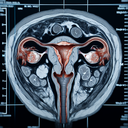

МРТ малого тазу у жінок

Магнітно-резонансна томографія (МРТ) малого тазу у жінок – це діагностичний метод, який використовує магнітні поля і радіохвилі для отримання детальних зображень внутрішніх органів та структур. Він особливо корисний для оцінки стану органів малого тазу, включаючи матку, яєчники, фаллопієві труби, сечовий міхур і навколишні тканини. ### Коли призначається МРТ малого тазу: 1...